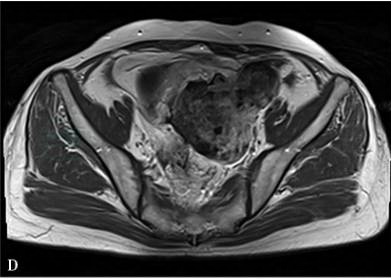

①盆腔较大肿物,形态不规则,边缘光滑或毛糙;②肿块大部分为实性,T1WI为等信号或稍低信号,T2WI为高信号,当病灶合并囊变坏死时,表现为T1WI低信号,T2WI为高亮信号;③增强扫描肿瘤的实性成分显著强化;④可见腹腔积液,早期腹膜及盆腔种植转移和侵犯邻近器官征象。(图1)

图1 卵巢癌肉瘤

A:盆腔内不规则形肿块,边界清楚,部分边缘毛糙,以实性成分为主,T1WI序列呈稍低信号;B:T2WI呈不均匀高信号;C:T2压脂序列呈不均匀高信号;D:不压脂增强扫描明显不均匀强化,内见斑点状未强化区;E、F:压脂增强矢状位及冠状位显示病灶更加清楚